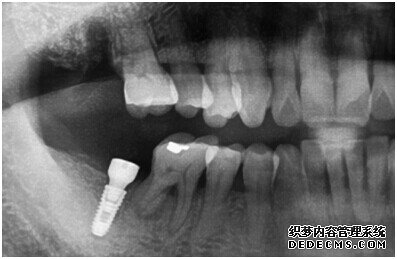

成功植入种植体后的效果图

种植体成功植入后的CT效果图

由CT片检查来看,刘女士口腔健康环境还是很好的,牙槽骨也适合种植牙的条件,而且由我们最后一颗牙是非常重要的,经过专家的建议和详细解释了原因之后,刘女士选择了美国百康种植牙。